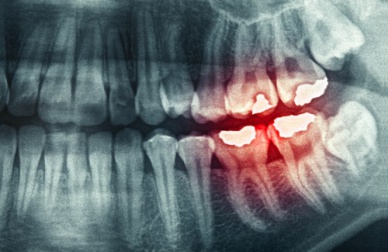

Esta situação de “apertar ou ranger” os dentes pode causar problemas na articulação temporomandibular, bem como inflamação dos músculos dessa zona. Além disso, pode haver o desgaste prematuro dos dentes que tem como consequência fraturas dentais.